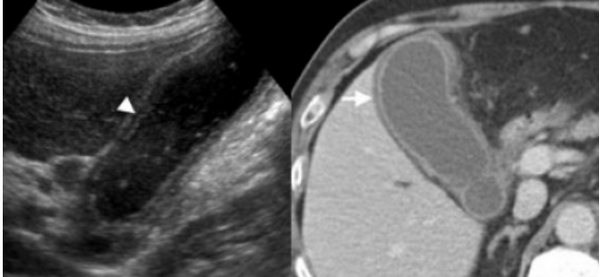

УЗИ некалькулезный холецистит.

Острый бескаменный холецистит возникает у пациентов во время поста, а также у пациентов, которые принимают лекарства, вызывающие холестаз. К признакам некалькулезного холецистита относятся все признаки острого калькулезного холецистита кроме наличия камней в просвете желчного пузыря, но при этом взвесь обычно присутствует.

74 — летнему мужчине выполнено УЗИ желчного пузыря. Диагноз: острый некалькулезный холецистит. На левой сонограмме стрелкой указано утолщение стенок желчного пузыря. В просвете желчного пузыря взвесь. На правой сонограмме у того же пациента при исследовании в доплеровском режиме выявлен еще один признак воспаления — гиперемия.